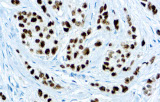

Anticorpos primários contra recetor de estrogénio (ER), recetor de progesterona (PR), HER2 e Ki-67 continuam a ser a pedra angular da classificação e decisões terapêuticas no cancro da mama. Estes anticorpos estão validados clinicamente e marcados CE/IVD para garantir deteção fiável e reproduzível de biomarcadores – crucial para orientar terapia hormonal e estratégias de tratamento direcionado.

- Elevada especificidade e sensibilidade: Permitem identificação fiável de subtipos tumorais e minimizam diagnósticos errados.

- Protocolos validados e uso clínico extenso: Asseguram reprodutibilidade entre laboratórios.